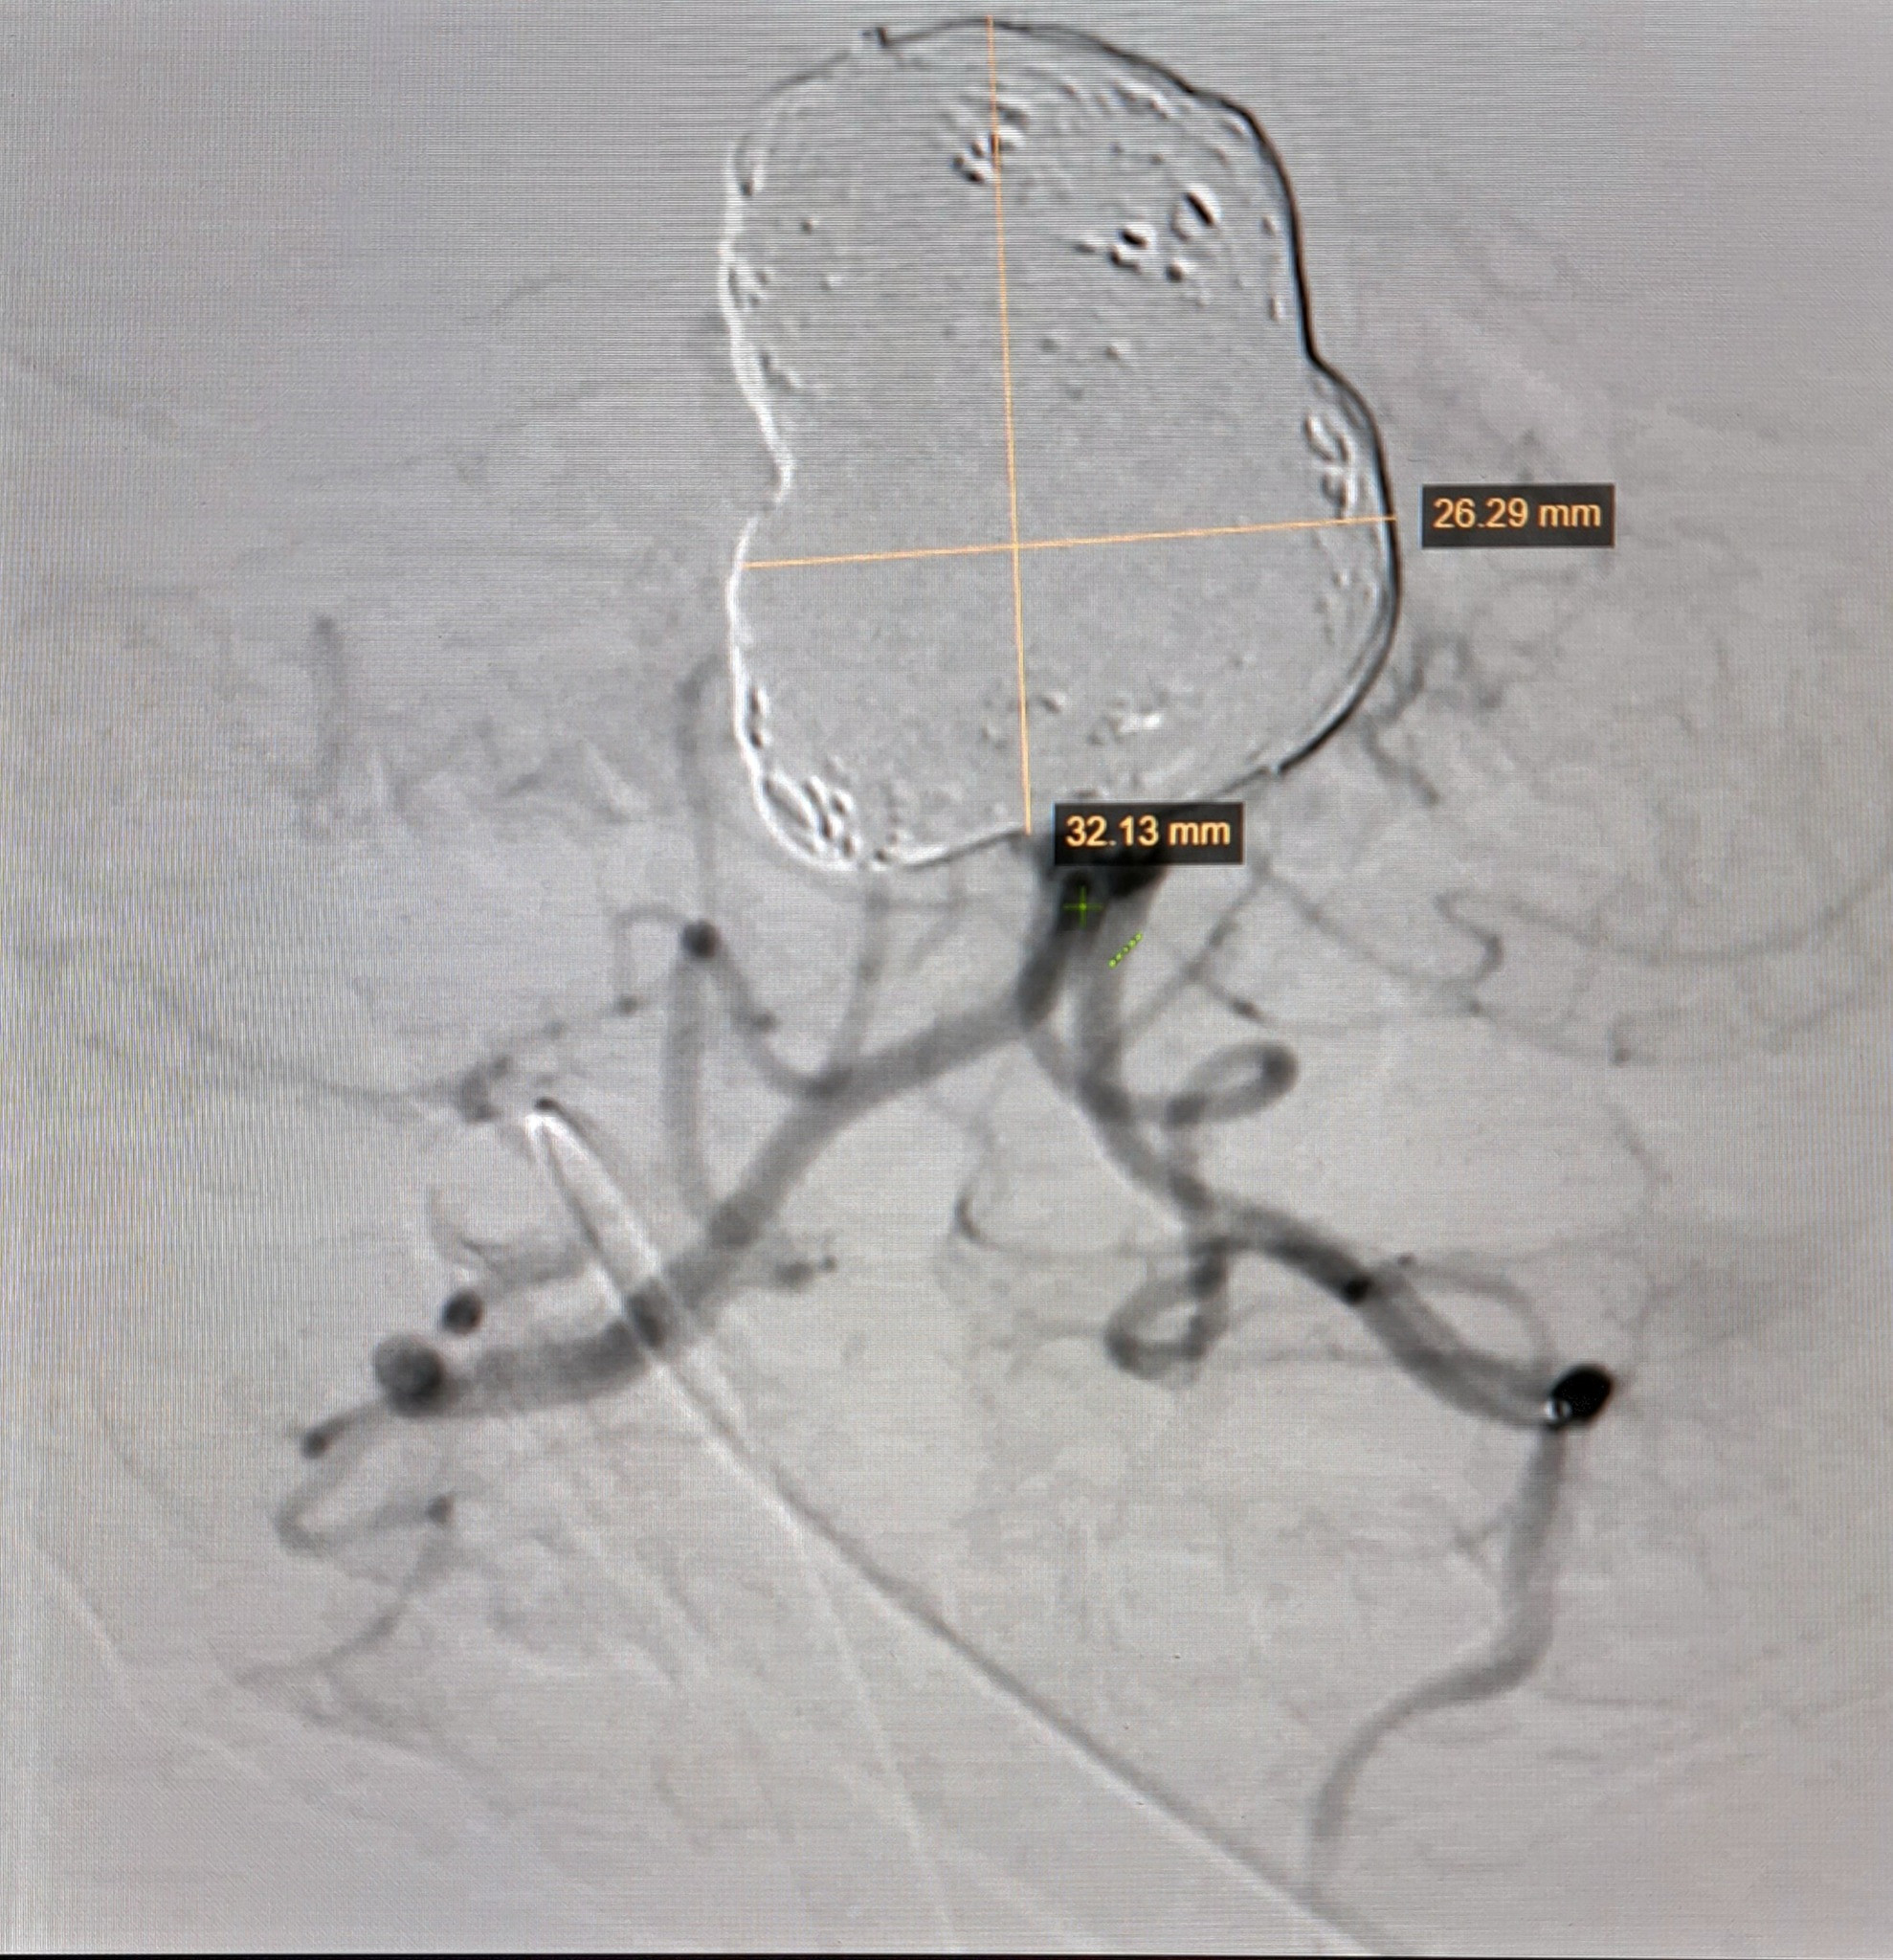

Tại Bệnh viện Nhi đồng 2 TP.HCM, bác sĩ chỉ định chụp CT Scan (chụp cắt lớp vi tính). Kết quả cho thấy bé K. bị xuất huyết dưới nhện, xuất huyết não thất hai bên. Qua hội chẩn, các bác sĩ tiếp tục cho chụp DSA (kỹ thuật chụp mạch máu xóa nền), phát hiện túi phình khổng lồ trong mạch máu não của bé.

Theo bác sĩ Cần, túi phình khổng lồ mạch máu não của bé có kích thước 32,13 x 26,29 mm, hiếm gặp và phức tạp. Bé mới 2 tháng tuổi, kích thước mạch máu rất nhỏ. Vì vậy, rất khó khăn khi luồng ống thông đi vào mạch máu, khiến thời gian thủ thuật kéo dài.

Ngoài ra, do kích thước túi phình lớn nên bác sĩ đã phải sử dụng đến 20 coils (vòng xoắn kim loại can thiệp nút túi phồng). Sau gần một tuần phẫu thuật, bé K. đã có nhiều tiến triển tốt và dự kiến xuất viện trong vài ngày tới.